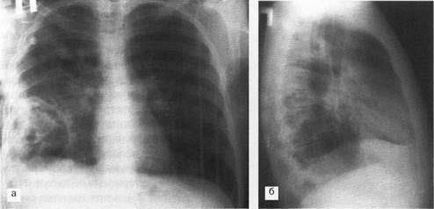

Caracteristica umbră inel închis cu pereți groși și o circulară decolorat în interior, de multe ori în combinație cu întunecare partea inferioară a formațiunii, nivelul separat orizontal de iluminare (fluid la interfața cu aer) da formarea parenchimului pulmonar cavitară în prezența posturilor cavitate cu aerul exterior. Formarea unor astfel de goluri tipice de abcese pulmonare (figura 2), și prezența în interiorul cavității blocări - abcese gangrenoasă (Figura 3) sunt drenate prin arborele bronsic.

Fig. 3. Imaginea cu raze X a pacientului Yu 21 de ani, în proiecțiile laterale (a) și laterale (b). În lobul inferior al plămânului drept, o cavitate mare cu pereți groși este definită cu câteva sechestre mici în interior. Abscesul gangrenos al plămânului drept